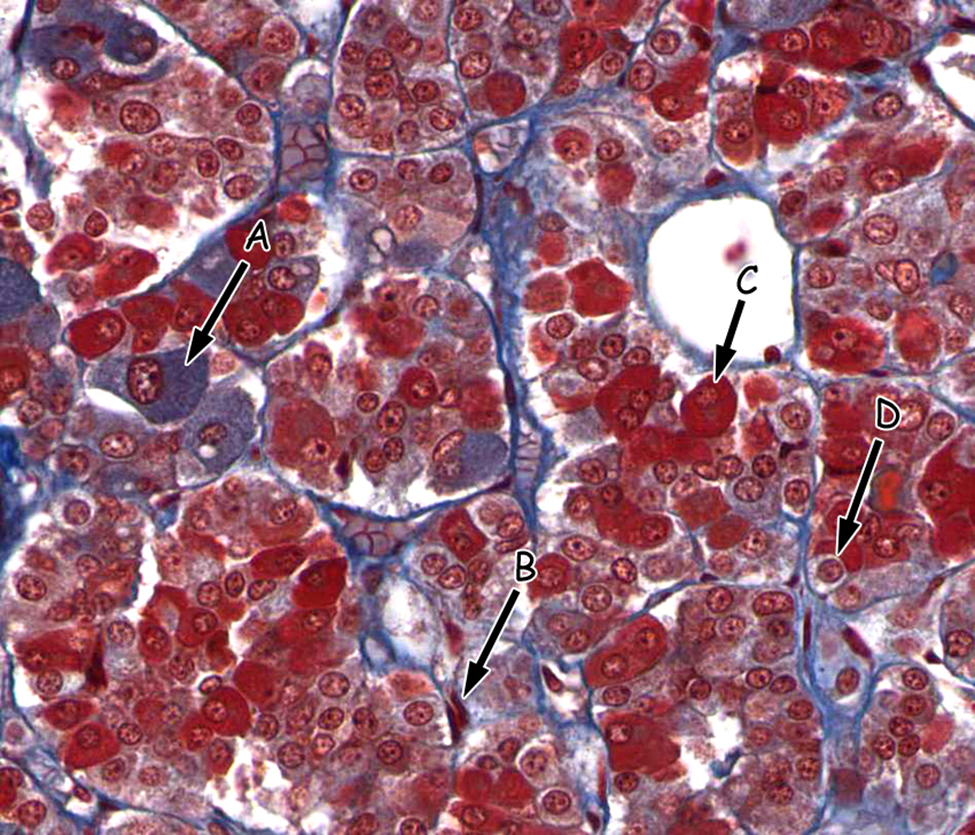

One possible cause of adrenal hyperplasia (hyperactivity) may be over-proliferation (e.g. a tumor) of which PITUITARY cell type indicated in this trichrome-stained section?

A. A

B. B

C. C

D. D

A

The zones of the adrenal gland are labeled in the attached image. Which zone synthesizes the largest amount of mineralocorticoids (such as aldosterone)?

A. A

B. B

C. C

D. D

E. E

B.B

Acromegaly leading to gigantism is caused by the excessive secretion of hormone from which of the following labeled cells?

A. A

B. B

C. C

D. D

C. C

The zones of the adrenal gland are labeled in the attached image. Overactivity of cells in which zone would cause virilization within women?

A. A

B.B

C. C

D.D

E.E

D. D